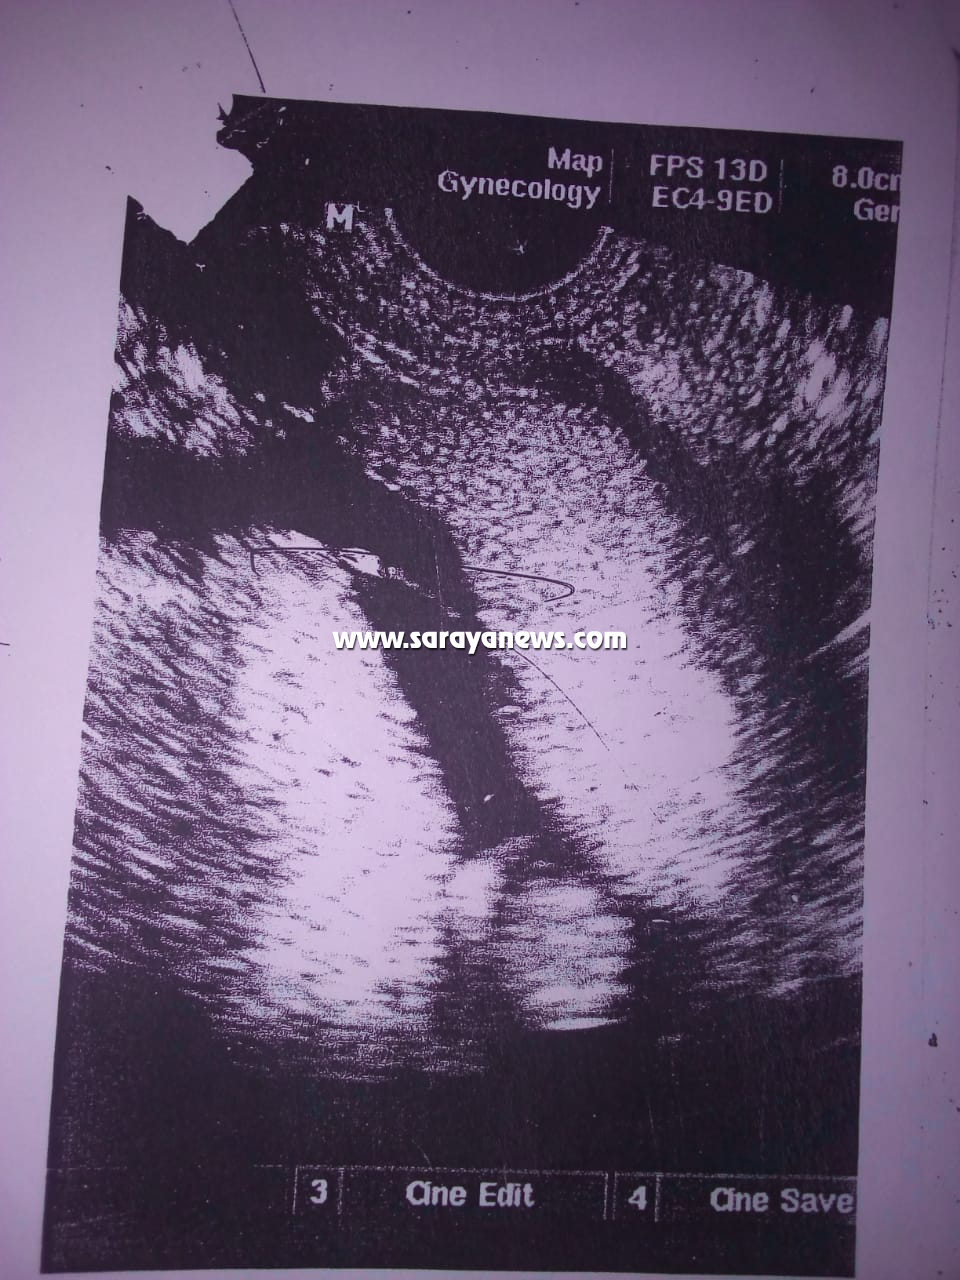

وبحسب رواية الأم نجلاء لسرايا قالت: "أنا كنت حامل بتوأم ومعي تقارير من بداية الحمل إلى آخر شهر من الحمل وحتى لحظات الولادة تفيد بأنني حامل بتوأم، وتضيف؛ كنت أراجع عند أكثر من طبيب نسائية ومعي صور شعاعيه للأجنة، وملف كامل من الطبيب المتابع لحالتي أثناء فتره الحمل وهو الطبيب ربحي خلف أخصائي النسائية والتوليد في المركز الطبي الفرنسي بمخيم غزة، حيث أخبرني في آخر مراجعة قمت بها لديه أن وضع التوأم جيد وكانت هذه المراجعة في آخر شهري الثامن، وبين لي حينها أن أوزان التوأم تصل لأكتر من(2700) غرام لكل طفل منهم، وأوضح لي في نفس الجلسة أن احد الأجنة نازل في الحوض -بمعنى اقتراب موعد الولادة– وأخبرني أنه يجب علي أن اذهب بعد عشر أيام من عيد الفطر لإحدى المستشفيات المتخصصة بالولادة، لتحديد موعد الولادة القيصرية، كون ولاداتي الستة السابقة كلها تمت بعمليات قيصرية للصعوبة الفائقة بولادتي الطبيعية".

تابعت نجلاء.. "توجهت بعدها إلى الطبيب منذر في عيادته الخاصة ببيته وهو طبيب نسائية وتوليد بمستشفى جرش الحكومي بتاريخ: (23 ـ 06 ـ 2018م) وتم فحصي من قبله حينها، وأكد لي أن التوأم بصحة جيده وبين أن طفل منهم رأسه نازل في الحوض، وأضاف لي انه احتمال أن ألد في وقت قريب، ونصحني بالتوجه إلى مستشفى جرش الحكومي، لحجز موعد لعملية الولادة القيصرية كون ولاداتي السابقات صعبة ولا تتم إلا بالعملية القيصرية، واتصلت على المستشفى في يوم ثلاثاء وأعطوني موعدا لعيادة الدكتور هاني بتاريخ: (3 ـ 07 ـ 2018م)".

تابعت نجلاء.. "ذهبت في نفس اليوم بعد زيارة الطبيب منذر إلى عيادة الدكتور عوف عفانة أخصائي النسائية والتوليد بعيادته الخاصة بمخيم غزة، حيث كنت أراجع عنده كل عشر أيام لأطمئن على أطفالي، وهذا الدكتور كان يتابع حالتي منذ الشهر الرابع إلى آخر يوم قبل ذهابي إلى الولادة ففحصني وطلب مني أن أُسرع بإجراء العملية مؤكدا لي أن أوزان الأجنة بازدياد مستمر".

وتابعت نجلاء.. "ذهبت في (3 ـ 07 ـ 2018م) إلى عيادة الدكتور هاني العقيلي وفحصني سريريا من خلال جهاز (الالترا ساوند) وقال لي: إن التوأم وضعه جيد ودقات القلب لديهما جيدة، وأضاف قائلا لي: إنا ما بقدر أعملك العملية أنتي حامل بتوأم وعندك ولادات قيصريه سابقة وأنا احتاج أكثر من دكتور وتخصص لمساعدتي في العملية هذه، وأعطاني تحويله طارئة إلى البشير، وقلت له بصير أروح اعملها في بديعة لأني أنجبت فيها مرات عديدة، فقال لي: ما في مشكلة روحي على بديعة".

تابعت نجلاء.. "عدت لبيتي من مستشفى جرش، وذهبت مساءً إلى الدكتور عوف وشرحت له عن التحويلة ووضع التوأم، فبادر بفحصي على جهاز (الالترا ساوند) وأكد أن أطفالي بخير وصحتهم جيده ونبضهم جيد وان أوزانهم اكتر من (2700 غم) لكل طفل وكرر طلبه مني الاستعجال بالعلية".

تابعت نجلاء.. "توجهت في (05 ـ 07 ـ 2018م) إلى مستشفى بديعة برفقة والدتي وزوجي ووصلنا المستشفى الساعة الثانية عشر ونصف ليلا، وأخبرتهم إنني حامل بتوأم، وتم فحصي من قبل الدكتور المقيم مثنى الشوحة في المستشفى حينها، وأكد لي أن توأمي أحياء ونبضهم موجود وجيد، وبين لي أن احدهم رأسه نازل في الحوض، وسألني مستغربا: هل زارعتيهم زراعه، وأجبته فورا: لا.. وأردفت تقول له: في عائلتي ننجب توائم مرات عديدة. وأضافت نجلاء.. في الأثناء قامت الدكتورة المقيمة رزان فؤاد حداد بإحضار أوراق وضعت بصمتي عليها".

تابعت نجلاء.. "حينها ذهب الطبيب المقيم واحضر لي دكتورة أجنبية اسمها   وفحصتني مرة أخرى، وسألتني: بتراجعي في أي مكان.. أجبتها لا ارجع، فقالت: ما معك أي ورقه من أي مركز صحي، فقلت لها: لا.. ما معي– حيث كنت خائفة ما يقبلوا يعملوا لي عملية لأني من جرش فأخفيت موضوع التحويلة وأوراق المراجعة لأنهم في المستشفى لا يستقبلون من خارج محافظة اربد- وتم عمل فحص لدقات القلب وتأكدوا أن التوأم بصحة جيدة".